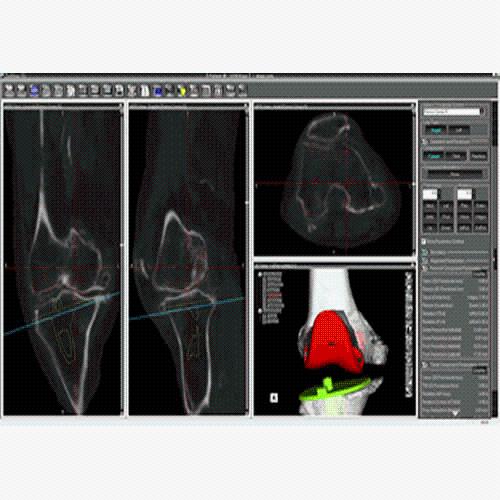

Segmentation

Segmentation of tissue (e.g., isolating the brain, differentiating gray and white matter) is performed using region-growing methods, filter operations as well as the application of 3D templates. Using the mouse it is very easy to explore a 3D volume with superimposed pseudocolor-coded statistical maps in a four-window representation showing a sagittal, coronal, transversal and oblique section. Based on a (segmented) 3D data set a three-dimensional reconstruction of the subjects' head and brain can be calculated and displayed from any specified viewpoint using volume or surface rendering.

Advanced segmentation tool means even higher quality segmentation of grey and white matter and boundaries.